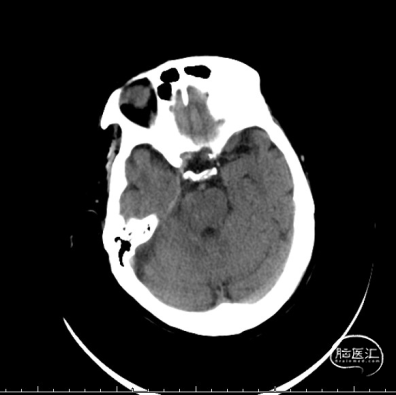

复查头颅CT示右侧额叶、尾状核头、侧脑室旁低密度灶。

头颅MRI提示额颞叶、基底节区多发脑梗死。

颅脑MRA+ASL提示右侧颈内动脉闭塞可能,大脑中动脉显影欠佳,伴低灌注。